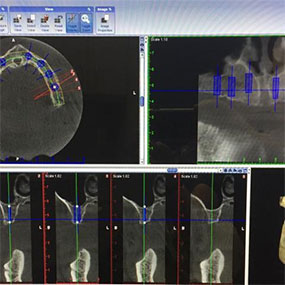

See a dentist in San Ramon, CA, for checkups, cleanings, fillings, crowns, and night guards that protect your bite. Our cosmetic services include whitening, bonding, and smile balancing that looks natural and confident. A dentist in San Ramon, California treats gum concerns, repairs chips or fractures, and offers same-day emergency visits when available. If dental anxiety has held you back, your dentist in San Ramon, California can provide nitrous or other sedation options to help you relax. Missing teeth affect how you eat, speak, and smile. After a thorough exam, a dentist in San Ramon, California reviews choices such as single dental implants, implant bridges, and implant-retained dentures. With 3D planning and a cleanable design, your dentist in San Ramon, California aims for strong chewing, stable comfort, and lasting value.